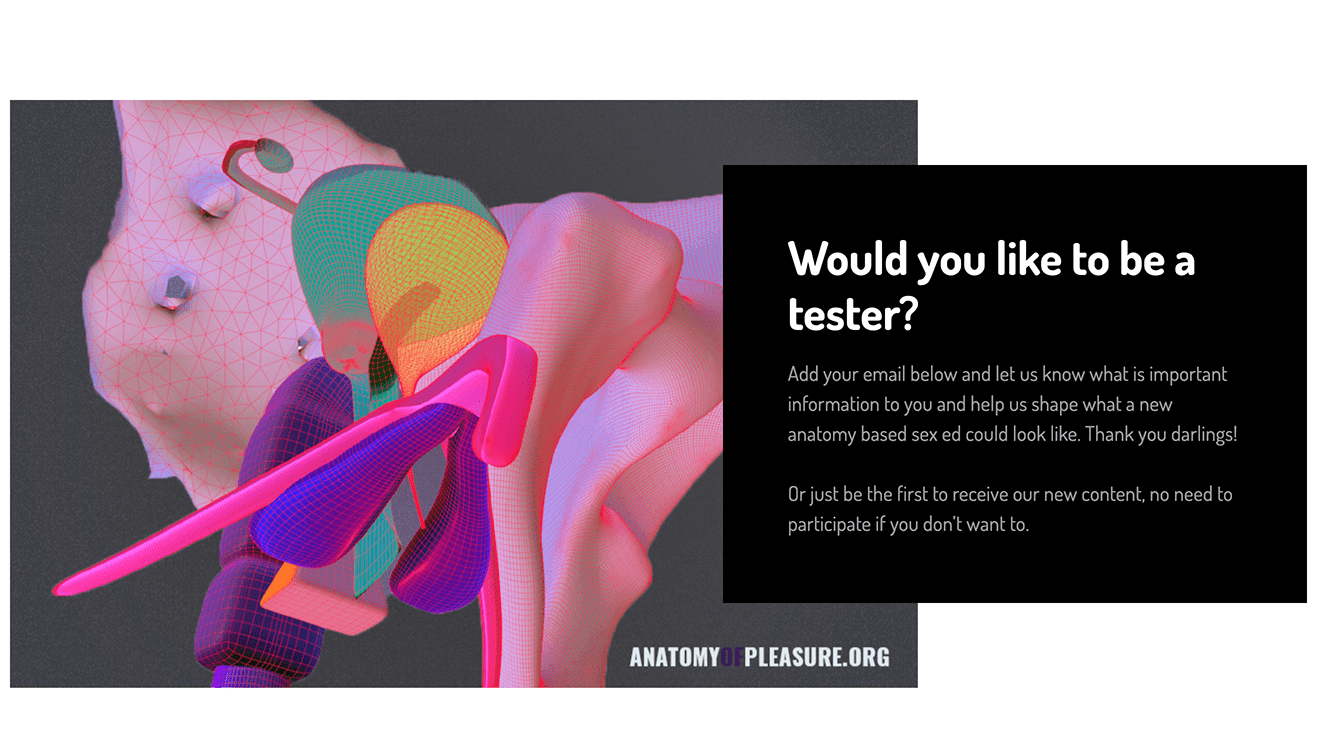

Pelvis

Pelvis Anterior

Pelvis Posterior

Pelvis, effect of relaxin hormone on pelvic ligaments

Line of Spence

Lightening

Pelvic floor

Pelvic Floor flexing movements

Effacement and Dilation of Cervix

Breach positioning

1-4th Degree tears

Internal and external fetal monitoring

Epidural

Latch and breastfeeding